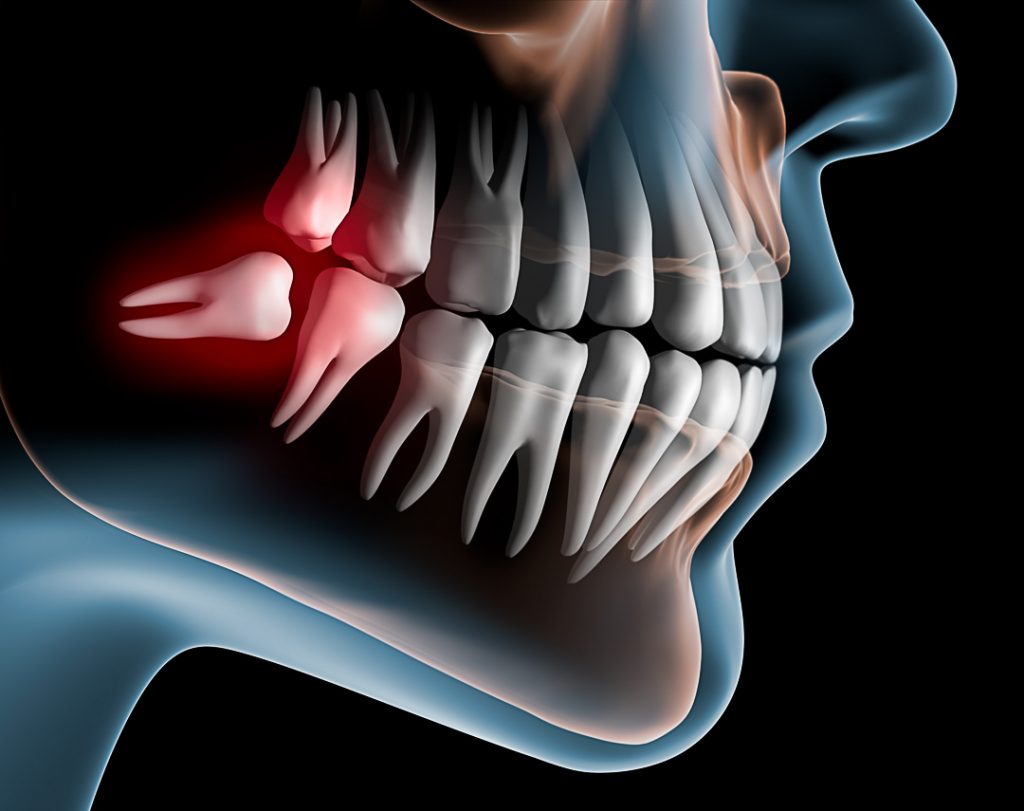

Os terceiros molares são os últimos dentes a nascerem entre 15 e 21 anos. É Bastante comum que não apontem totalmente para fora quando isso acontece o dente fica impactado, torto e retido dentro do osso é o que chamamos dente incluso.

Um dente incluso pode ficar na horizontal (deitado) dentro do maxilar o que contribue para infecção e dificuldade de remoção.

A falta de espaço para o siso nascer no lugar certo atrapalha seu desenvolvimento, nesse caso ele passa a empurrar os outros dentes na tentativa de encaixar na arcada causando cáries nas raízes dos dentes vizinhos desalinhamentos e infecções como a pericoronarite.